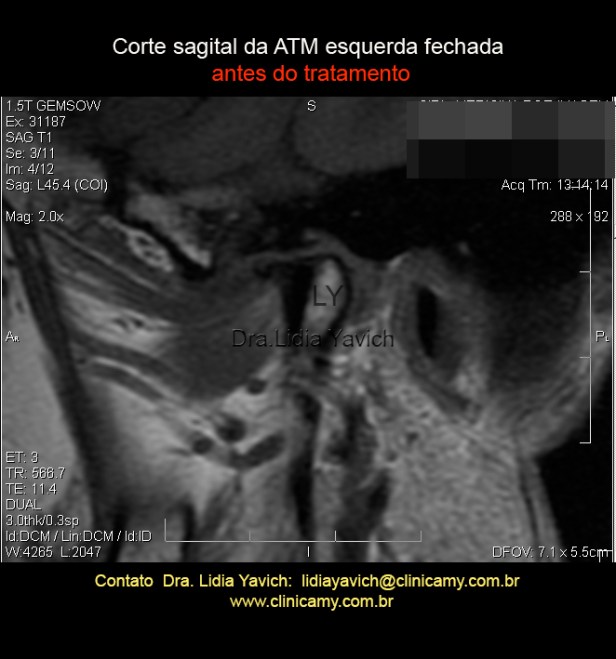

13 RNM  ESQ  INICIAL

RNM: corte sagital da ATM esquerda em boca fechada. Existe uma importante irregularidade de contornos da porção superior do côndilo mandibular, com formação de osteofito anterior.

Existe uma retificação da eminencia articular.

O disco tem dimensões reduzidas encontrando-se deslocado anteriormente SEM REDUÇÃO  nas manobras em boca aberta.

PODE SE OBSERVAR UM IMPORTANTE HIPOSSINAL COMPATÍVEL COM NECROSE AVASCULAR.

Osteonecrose da cabeça da mandíbula corresponde à morte do tecido ósseo, também chamada de necrose avascular.

A alteração na medular óssea do côndilo mandibular é uma possível fonte de dor da ATM.